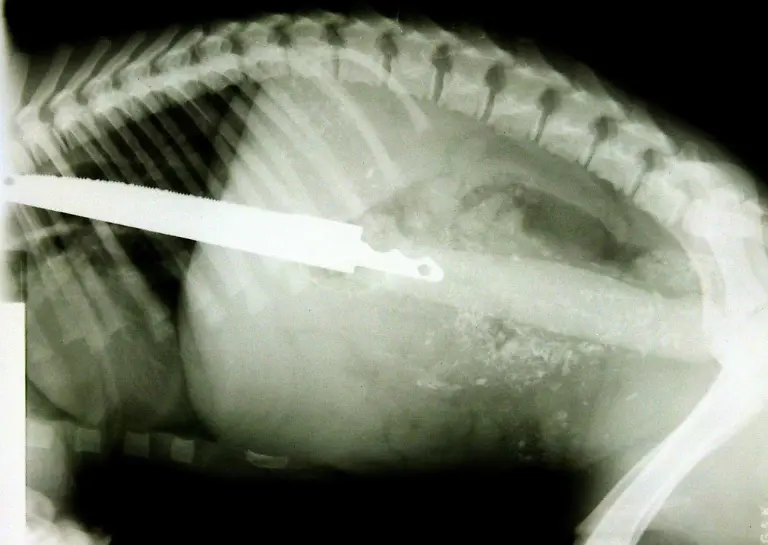

Nägel, Messer, TelefoneWas Röntgenstrahlen zum Vorschein bringen

Nicht immer zeigen Röntgenaufnahmen das, was man von ihnen erwartet. Oft kommt es zu Bildern, die selbst hartgesottene Betrachter zum Schaudern bringen - und der Wissenschaft Rätsel aufgeben.